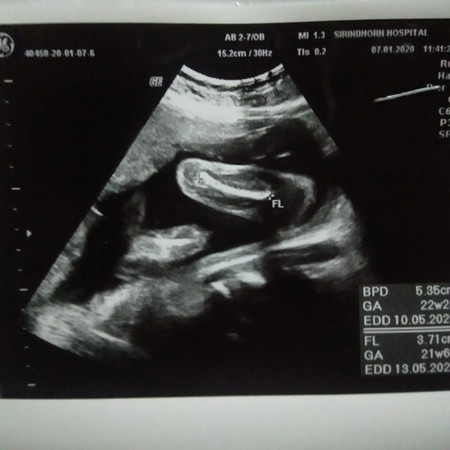

อัลตราซาวนด์

ใครดูเป็นบ้างค่ะ..รูปนี้คือส่วนใหนของน้องค่ะ

หน้าจะช่วงขา รึไม่ก็ช่วงแขนน่ะค่ะ เพราะตรงสีขาวๆเหมือนกระดูกเลย